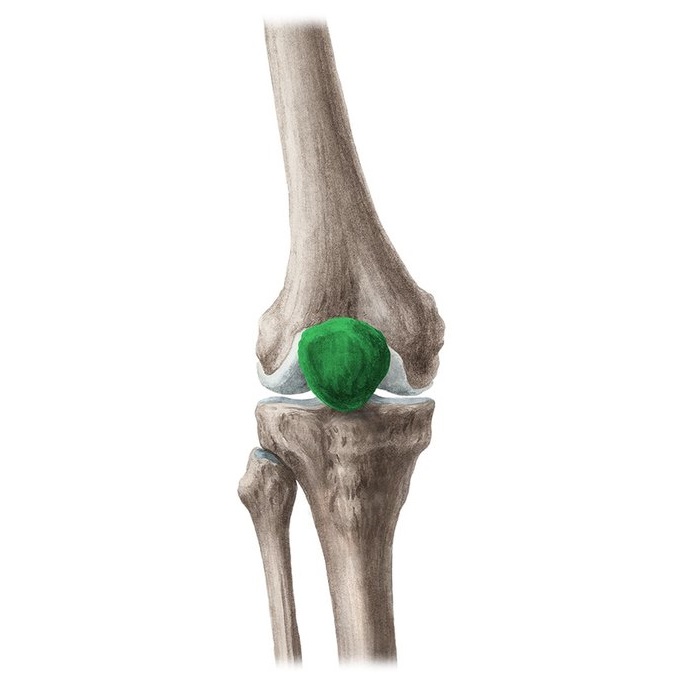

Bursitis

BURSITIS Y SINOVITIS

PATELOFEMORAL

S. PATELOFEMORAL